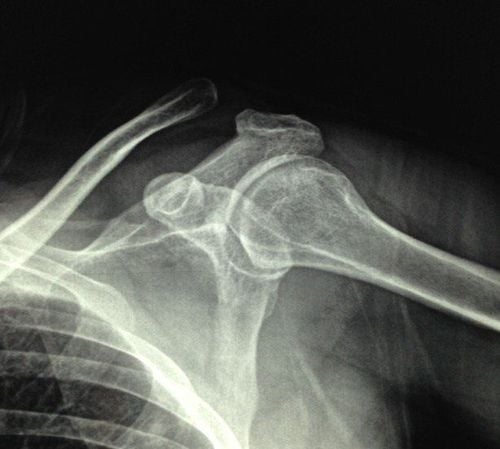

Hình ảnh trật khớp cùng đòn trên X-quang

Việc chẩn đoán trật khớp cùng vai đòn được thực hiện dựa trên các triệu chứng lâm sàng của người bệnh và kết quả xét nghiệm cận lâm sàng là chụp X – quang.

Một số kỹ thuật chụp X – quang được sử dụng trong chẩn đoán gồm:

• Kỹ thuật chụp X – quang khớp vai 3 tư thế: X – quang xương bả vai chữ Y, X – quang vai thẳng, X – quang nách.

• Kỹ thuật chụp X – quang Zanca: Giúp quan sát vị trí đầu khớp cùng đòn tốt hơn, kỹ thuật này tương tự kỹ thuật X – quang vai thẳng, tuy nhiên đầu phát tia chếch về phía đầu 10 độ.

• Kỹ thuật chụp X – quang stress.